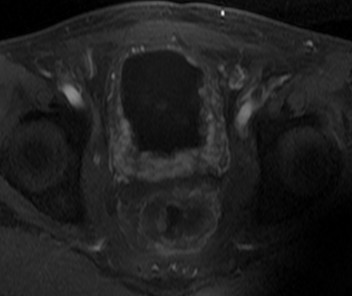

患者男性,63岁。诊断:直肠癌术后Ⅳ期,膀胱、盆腹腔及骨多发转移。患者2013年3月确诊后,行放化疗,后吃中药治疗,2015年12月病情恶化。2016年1月,盆腔MRI检查提示直肠癌侵及膀胱及周围组织,伴骶前转移及骶骨转移。2016年3月,CT检查提示直肠占位病变伴膀胱、前列腺、部分骶椎输尿管受侵,右侧大网膜强化结节,转移不除外,肠系膜及腹膜后淋巴结增大。肠镜检查提示肛管见菜花样肿物,肛管狭窄。化疗一疗程后,患者不能耐受而终止。为寻求下一步治疗方案,患者找到全球肿瘤医生网A45专家,经过中美癌症专家综合会诊,制定A45治疗方案。

患者于2016年6月开始A45治疗,一个疗程后复查,膀胱及直肠病灶明显缩小,肛周复发灶较前缩小,血尿症状消失,疼痛症状消失,其他症状显著缓解。